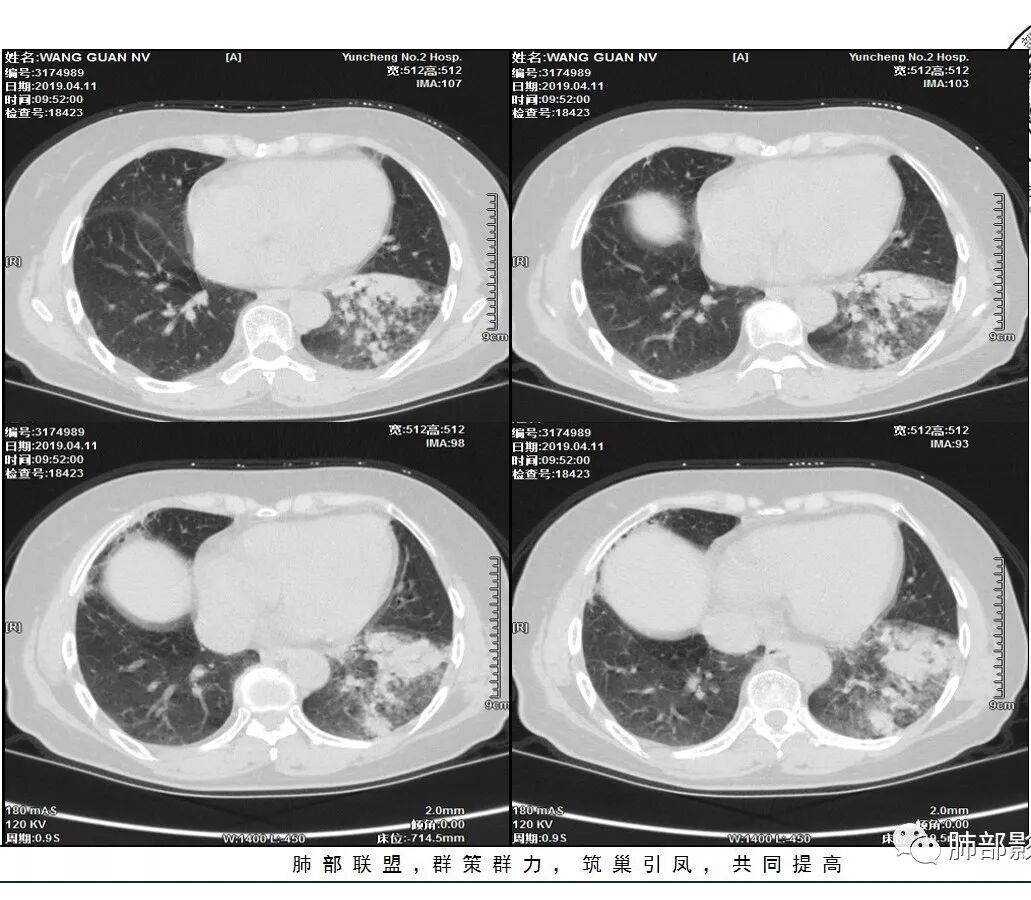

胸CT:左下叶实变影及磨玻璃影,小叶间隔增厚,内部支气管扩张、僵直。左肺门淋巴结肿大、钙化。考虑肺腺癌?合并感染

胸CT:左下叶基底段支气管狭窄,沿支气管分布斑片实变影、网格影、磨玻璃影,支气管充气征,无重力效应,左肺门淋巴结肿大、钙化。

1、主病灶  左下叶斑片状、大片状致密影

2、两肺马赛克灌注

3、两侧肺门区钙化淋巴结

2.左肺下叶片状影及多数有边界的结节影,较散,多形性,密度不均(注意许多老师提到这个特点还是比较明显的)。左肺下叶体积未见缩小。

3.病灶强化比较明显。

4.左下叶支气管壁增厚,管腔不均匀狭窄,没有堵塞

5.肺门纵隔见增大钙化淋巴结。提示曾经存在慢性病损可能。